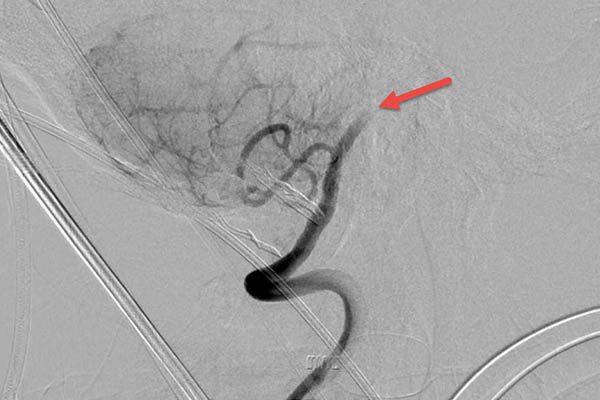

In a procedural suite at UCH, neurosurgeon Joshua Seinfeld, MD, looked at images that showed a complete blockage of Cohen’s left vertebral artery, which supplies blood to the brain stem and left occipital lobe. It had been 14 hours since the clot shut down the artery – a dangerously long period of time. Seinfeld used a stent retriever to pull the blood clot out of the artery, but his work wasn’t finished. The vessel was badly diseased and still couldn’t accommodate much blood flow. Seinfeld performed a balloon angioplasty to widen it.

The stroke damage was extensive, Seinfeld said. Describing Cohen’s case later, he pointed to bright areas on an image of Cohen’s brain – signs of a “completed stroke” that left dead tissue. Had there been more of it, the clot-removal and angioplasty procedures wouldn’t have happened, Seinfeld said.

“Restoring blood flow to dead brain tissue will cause a hemorrhage,” he said. “In [Cohen’s] case, it was risky to remove the clot, and we knew he could do poorly, but if we left it alone, he would die. When there is an occlusion in the areas of the brain where he had his stroke, we tend to consider treatment for a longer period of time than for strokes at the top or the front of the brain because people can have a [much better] response.”